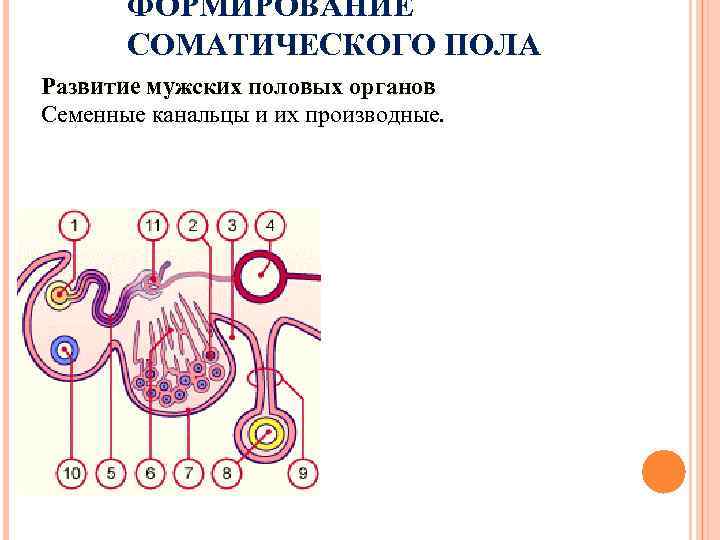

ФОРМИРОВАНИЕ СОМАТИЧЕСКОГО ПОЛА Развитие мужских половых органов Семенные канальцы и их производные.

ФОРМИРОВАНИЕ СОМАТИЧЕСКОГО ПОЛА Развитие мужских половых органов Семенные канальцы и их производные.